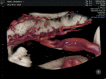

Diagnostic ultrasound (DUS) is, arguably, the most common technique used in obstetrical practice. From A mode, first described by Ian Donald for gynecology in the late 1950s, to B mode in the 1970s, real-time and gray-scale in the early 1980s, Doppler a little later, sophisticated color Doppler in the 1990s and three dimensional/four-dimensional ultrasound in the 2000s, DUS has not ceased to be closely associated with the practice of obstetrics. The latest innovation is the use of artificial intelligence which will, undoubtedly, take an increasing role in all aspects of our lives, including medicine and, specifically, obstetric ultrasound. In addition, in the future, new visualization methods may be developed, training methods expanded, and workflow and ergonomics improved.